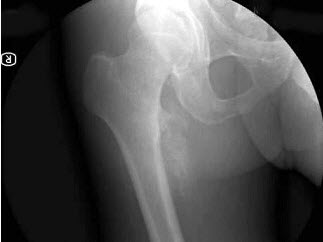

32、单项选择题

女,35岁,摔伤后左髋部剧痛,活动受限6小时,结合影像学检查,最可能的诊断是()